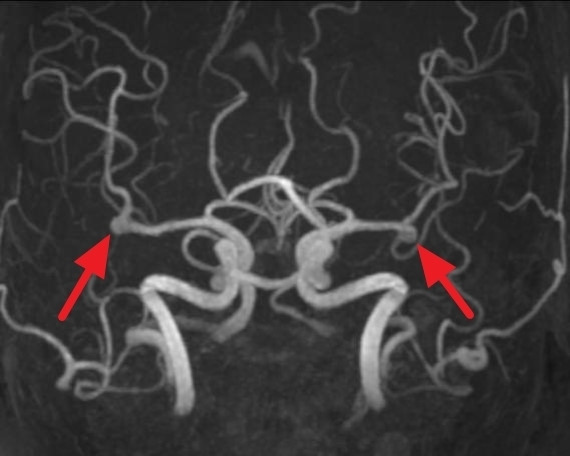

뇌동맥류를 정확하게 진단하기 위해서는 뇌혈관의 상태를 상세히 확인할 수 있는 검사가 필요합니다. 그 중 하나가 뇌혈관 조영술입니다.

뇌혈관 조영술은 대퇴동맥을 통해 카테터라는 2mm 내외의 관을 삽입한 후 조영제를 주입하고 X-ray를 촬영하여 뇌혈관의 상태를 파악하는 검사입니다. 이 검사는 뇌동맥류, 뇌혈관 협착, 뇌동정맥 기형 등의 진단에 매우 정확하며, 치료 계획을 세우는 데 필수적입니다.